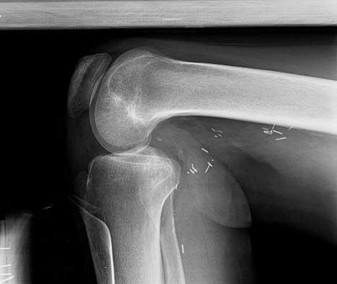

Match the description with the corresponding response. Question 29 of 100

Neural structure most likely damaged as a result of this injury (Figure 29)

PREFERRED RESPONSE: 3- Sciatic nerve, peroneal division

The posterior position of the sciatic nerve in relation to the acetabulum and the lateral peroneal division makes the peroneal division of the sciatic nerve the portion of the nerve that is most likely to be injured in a posterior traumatic hip dislocation, accounting for up to 10% of concomitant nerve injuries with posterior hip dislocation. The corona mortis is an anatomic variant that results in vascular anastomosis between the obturator and either the external iliac or inferior epigastric arteries. This variant occurs in approximately 80% of patients and varies in its position, being located 4 cm to 9 cm lateral to the symphysis pubis. The obturator vascular bundle is situated in the fat medial to the obturator internus muscle and must be mobilized to access the quadrilateral plate. Dissection may be carried out both above and below this vascular leash. The Kocher-Langenbeck approach is indicated for fractures involving the posterior wall and/or posterior column of the acetabulum and for both column fractures that require direct posterior visualization. This approach is not indicated for direct reduction of the anterior wall or column when direct visualization is required anteriorly. The L5 nerve root is located on the anterior sacrum and is indicated by the arrow.

The position of this neural structure must be considered whether the surgeon is stabilizing 31 the sacroiliac (SI) joint with percutaneous iliosacral screws or with anterior SI plating through the lateral window of the ilioinguinal approach.